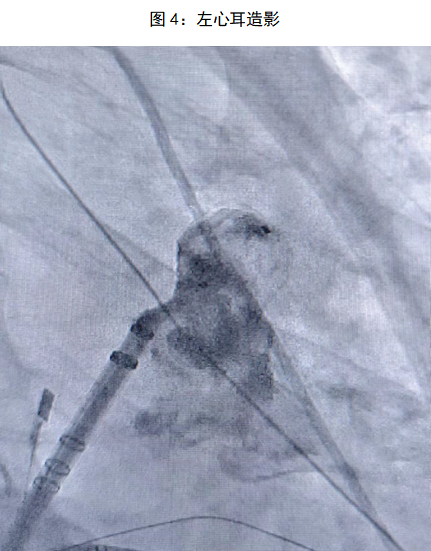

术前对患者进行充分评估,在进行完善的术前检查和全面的术前准备后,手术顺利启动。手术分为两个部分:首先是房颤射频消融,术中使用pentaray导管在Carto3三维系统下,重构建左心房三维解剖图(FAM)同时采集左心房电压基质,在构建右下肺静脉时转为房颤心律,再使用消融导管对左房右肺静脉顶部和侧壁以及左肺静脉嵴部和后壁部位进行逐点消融,左侧和右侧肺静脉均实现单圈隔离,整个射频消融时间控制在90min内。射频消融完成后,朱舜明副主任立即开始左心耳封堵手术。通过在同一个房间隔穿刺位点交换左心耳封堵鞘,造影显示心耳形态呈反鸡翅型,测量左心耳开口为17mm,可用深度为16mm,结合术前三维重建模型及术中心腔内超声(ICE)结果,选择20mmWATCHMAN FLX左心耳封堵器。送入WATCHMAN FLX输送系统,并在ICE及DSA辅助下进行精准定位,ICE多角度查看封堵器位置形态良好,封堵伞展开无漏肩,无残余分流,压缩比16%,牵拉试验稳定,牵拉后无明显位移,符合释放标准PASS原则。随后释放封堵伞,最终成功完美封堵左心耳。